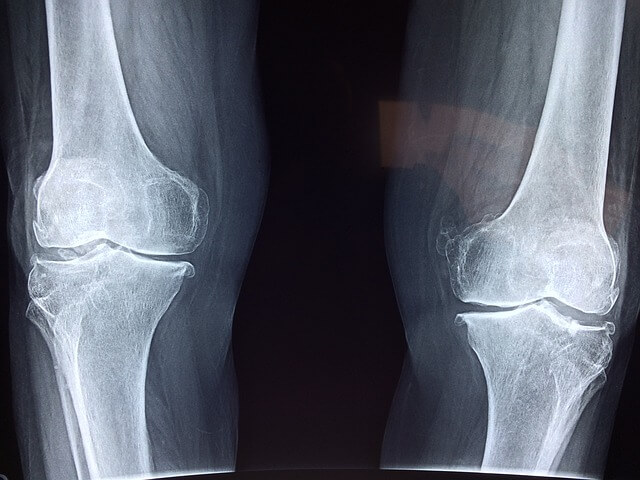

- 관절 통증 완화 : 콘드로이친은 관절의 윤활을 도와주어 통증을 줄이는 데 기여합니다. 특히 퇴행성 관절염 환자에게 효과적이라는 연구 결과가 있습니다.

- 연골 보호 : 콘드로이친은 연골의 구조를 유지하고 손상을 방지하는 데 도움을 줍니다. 이는 관절의 기능을 향상하고 노화로 인한 연골 손실을 늦추는 데 기여합니다.

- 염증 감소 : 콘드로이친은 염증을 줄이는 데 도움을 줄 수 있으며, 이는 관절의 통증과 부기를 완화하는 데 기여합니다.